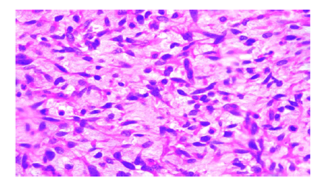

Figure 3: Additional Microscopic View

Description: Another microscope image (H&E stain, 200x magnification) of a different section of the tumor, also showing a high-grade spindle cell sarcoma. This view reveals a highly cellular tumor with spindle-shaped cells in a bundled pattern. The cells have long, darkly stained nuclei with moderate to significant irregularity and little surrounding material. Fibrous tissue is seen in the background, stained in the usual pink-purple H&E colors. Dividing cells and necrotic tissue aren’t obvious in this section, likely due to differences in the sampled area, but the cell structure matches the sarcoma seen in Figure 2.

Soft tissue sarcomas in children are a diverse group, and spindle cell sarcomas are a rare type within this category. The MRI (Figure 1) revealed a mass with uneven borders and mixed signal patterns, which is typical for cancerous soft tissue tumors and helped guide the decision to biopsy and operate. Under the microscope, the tumor showed spindle-shaped cells, frequent cell division, and areas of tissue death, all signs of an aggressive cancer that needed quick action [2]. The microscopic images (Figures 2 and 3) highlight the spindle cell structure, with Figure 2 showing a few dividing cells and Figure 3 emphasizing the dense, bundled cell arrangement. The lack of visible cell division or dead tissue in Figure 3 is likely due to differences in the sampled area, as tumors can vary across sections. The surgical specimen (Figure 4) reveals a tumor with bloody and fibrous areas, matching the aggressive nature of high-grade sarcomas. Special staining was key in ruling out other tumors like rhabdomyosarcoma, which was excluded due to the lack of myogenin staining and only focal desmin positivity, and synovial sarcoma, which was less likely due to the absence of epithelial markers and the overall staining pattern [3]. The positive outcome here highlights the importance of removing the tumor with clear margins and using additional treatments like chemotherapy, as recommended by current guidelines [4].